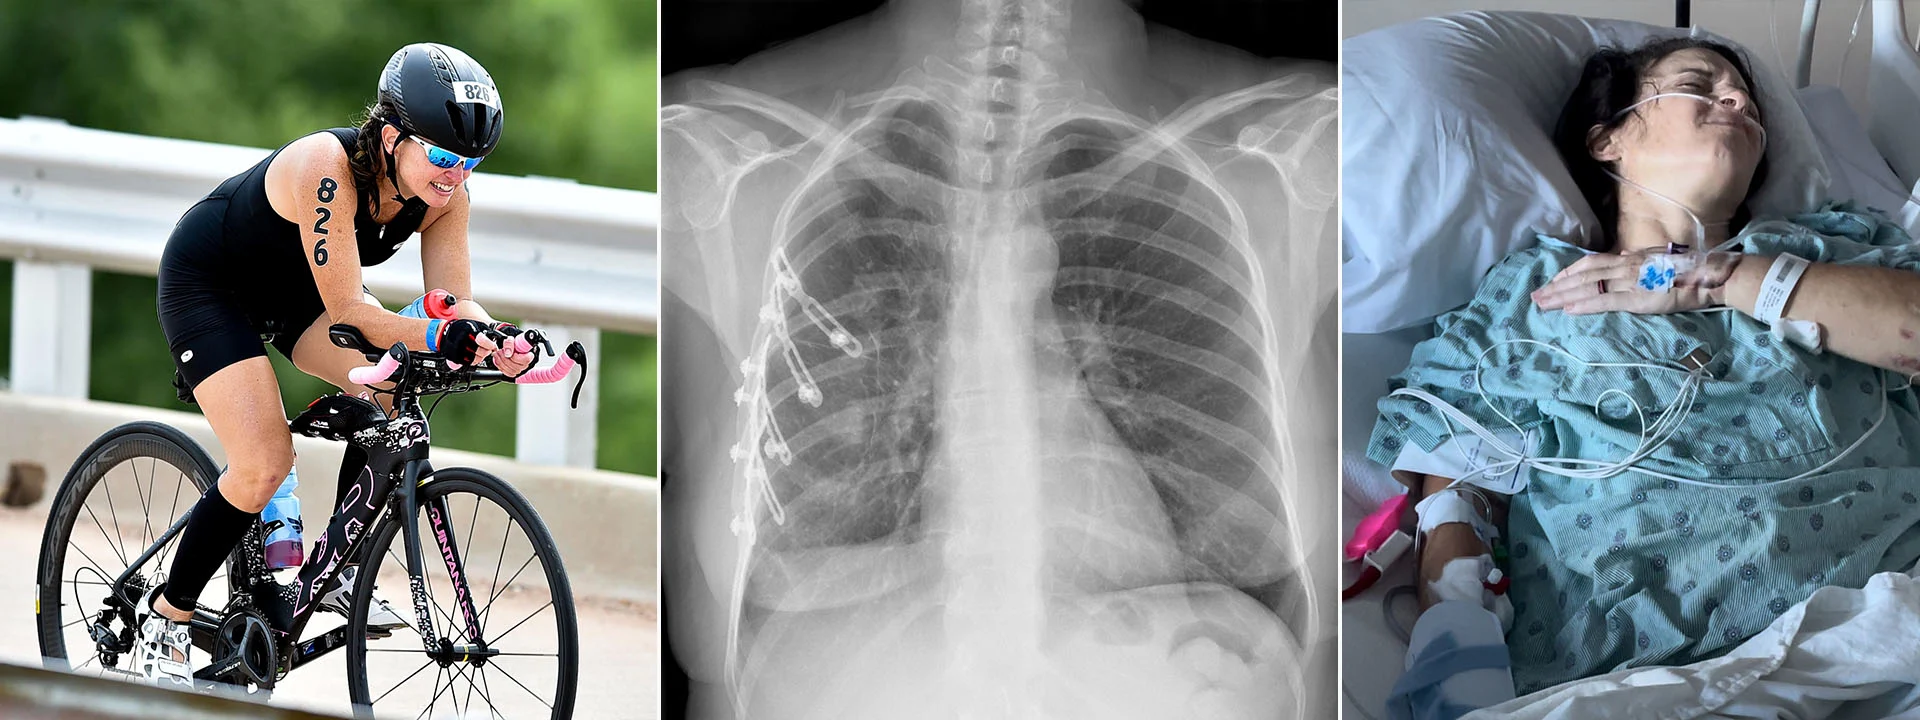

Nancy Rehm, an accomplished multi-sport endurance athlete, was one mile from finishing a 51-mile bike tour in Waco, Texas, when she was involved in a near-fatal collision with an SUV. Thrown twenty feet and knocked unconscious, her life changed in an instant.

She arrived at a trauma center in critical condition. She suffered a concussion, a broken shoulder, and the right side of her chest was shattered. Her lungs struggled to inflate due to her injuries, allowing blood and air to collect in her chest cavity, putting her life in immediate danger.

Rehm’s case was extreme. She had nine broken ribs, seven of which were fractured in multiple places. This severely limited her ability to breathe.

"The immediate aftermath marked some of my darkest days both mentally and physically. I didn't know how to move forward," she shared. Doctors warned that traditional surgery would likely mean dealing with chronic pain for the rest of her life, making everyday activities difficult—let alone competing in triathlons.

Nancy Rehm's passion for triathlons shines through as she races in an Ironman event in Lubbock, Texas.

While healing from both the surgery and the accident's trauma was challenging, Rehm's progress has been remarkable.

“Every medical professional I’ve encountered along the way is beyond shocked at the pace of my recovery,” she said. “They say that they wouldn’t normally see this kind of improvement at all, let alone within five or six months.”

Less than ten months after surgery, Rehm was in Spain for the World Triathlon Multisport World Championships, a race she qualified for before her accident. She participated in the Parade of Nations with her husband and daughter, and all three competed in the race. Rehm recounted that crossing the finish line of the race felt like a dream.